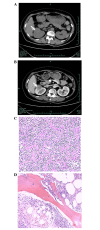

(A) Computed tomography (CT) revealing a 3.6-cm mass at the right kidney without associated hydronephrosis or ureteral obstruction. (B) Contrast-enhanced CT showing that the mass of the right kidney exhibited continuous progressive enhancement, with a value of 100 HU in the corticomedullary phase. (C) Histological evaluation of the nephrectomy specimen showing a diffuse large B-cell non-Hodgkin's lymphoma. (D) Bone marrow biopsy showing no morphological involvement of lymphoma.